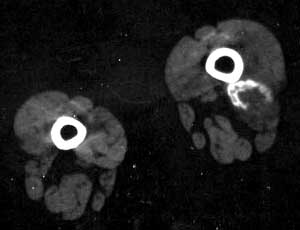

女,16岁。 左大腿下段肿痛半月余,局部肿、痛、热,不发红.

骨化性肌炎分4型:外伤性骨化性肌炎;伴有神经症

状的骨化性肌炎;进行性骨化性肌炎;原因不明性骨化性

肌炎\"4种类型中最常见是外伤性骨化性肌炎,常只有单一

病灶,一般多是由外伤引起的,肌肉内出血而发生\"出血后血液不被吸收,逐渐的钙化和骨化\"一般在外伤后不久,即可在

x线上显示局限性肿块,经3~4周后密度增加,并在软组织

内出现模糊的骨化影,可呈条状或层状沿骨干排列\"邻近的

骨也可能见到骨膜反应,且骨化的一处或数处可与邻近的骨

骼相连\"伤后6~8周肿块边缘为境界清晰的致密骨所包绕,

而中心部分可以发生囊变形成蛋壳样钙化性囊肿\"伤后5~6

周进一步骨化成熟,钙化性肿块缩小并与邻近骨质之间可见

透光带阴影\"1年后,钙化性肿块往往吸收消失,也可残存骨